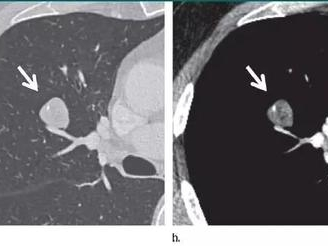

图1:肺错构瘤